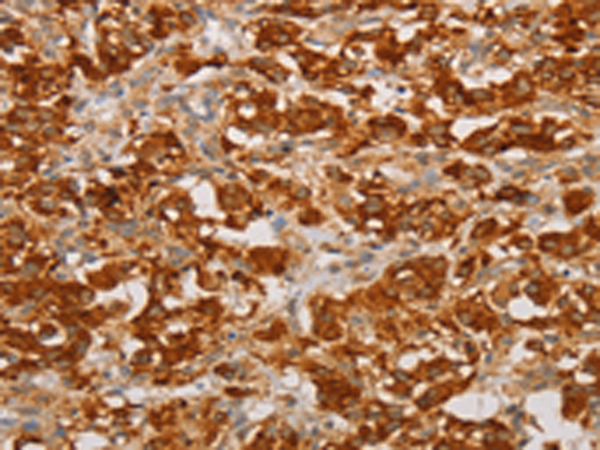

分类: 科研抗体货号: P08025别名: SK 2; SK-2; SPK 2; SPK-2应用: WB,IHC反应种属: Human, Mouse